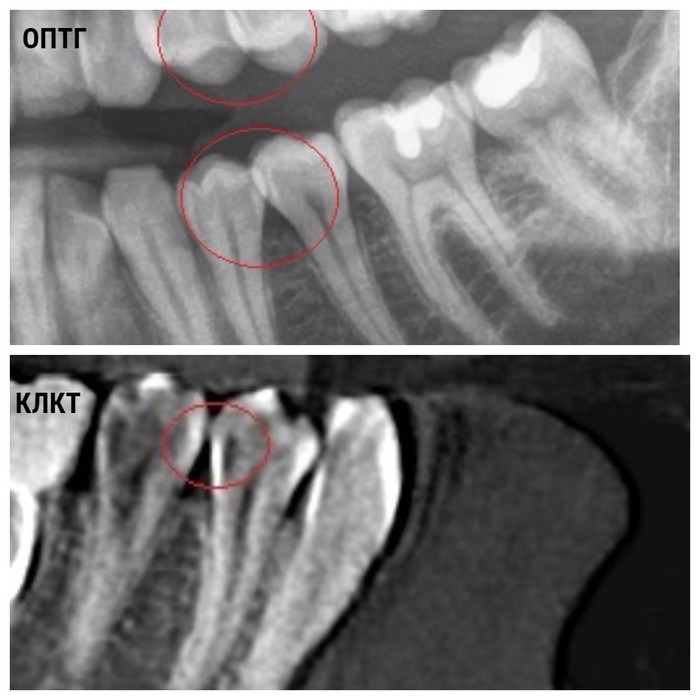

Например, панорамный снимок (ортопантомограмма, ОПТГ) за счёт наложений даёт около 50% информации о зубочелюстной системе. А компьютерная томограмма (КТ, КЛКТ) - от 80% до 95%. Скрытый кариес в начальных стадиях виден только на КТ. Кружками отмечена зона наложения на ОПТГ и эта же зона на КЛКТ без наложений. Тёмное пятно на боковой стенке зуба - это кариозная полость.